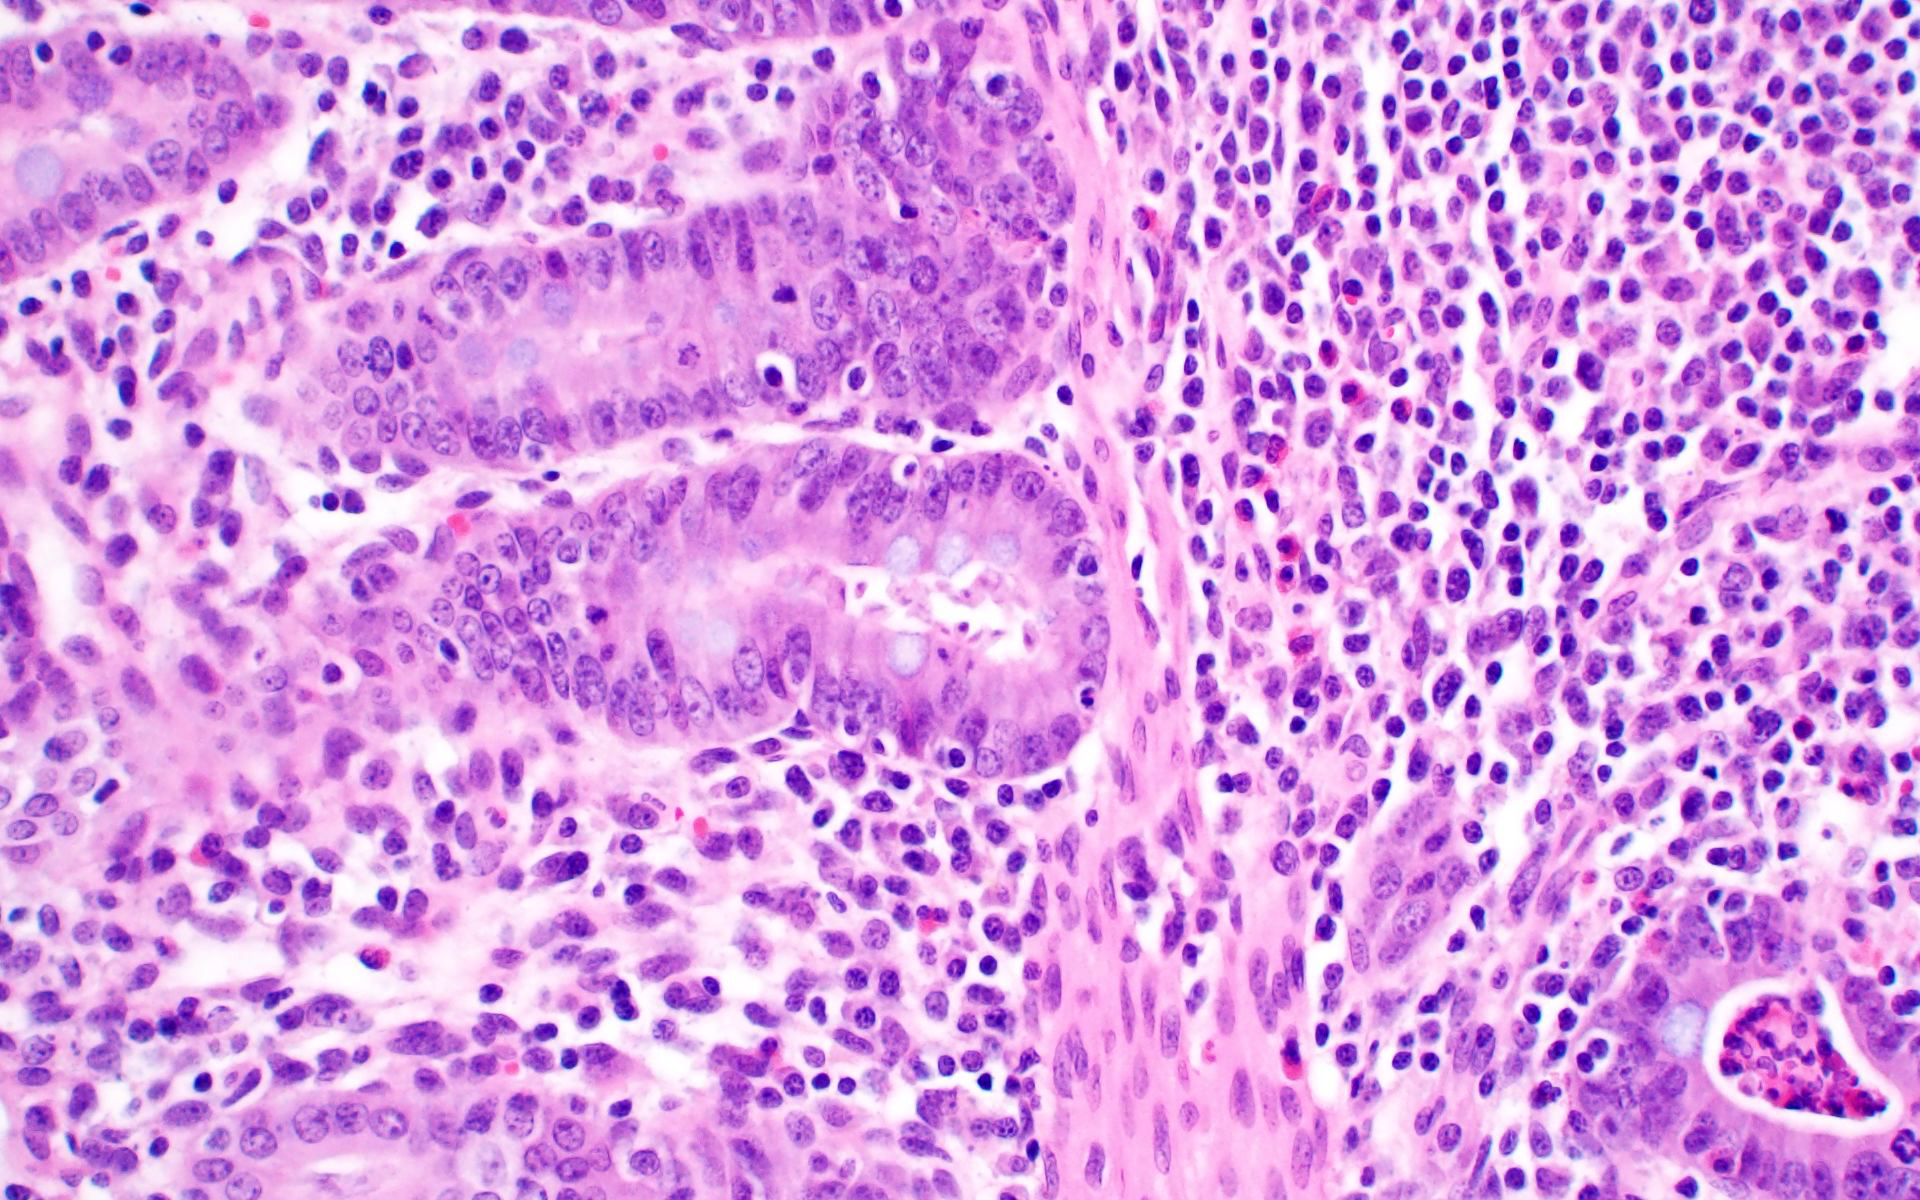

Ileum: In several sections, there is moderate multifocal blunting and fusion of villi with a crypt: villus ratio of 1:1. Apical enterocytes are often moderately attenuated with loss of the brush border and reduced apical cytoplasm. In some sections, these cells have a profound number of intracellular but extracytoplasmic 1-2 um circular eosinophilic apicomplexan organisms with 0.5 um basophilic nuclei (Cryptosporidium sp.). In other sections, these cells contain numerous larger apicomplexans with varied life-stages apparent including: 10 x 5 um curvilinear binucleate meronts (type I meronts), 4 x 12 um curvilinear uninucleate merozoites (type I merozoites), 9 x 6 um ovoid multinucleate meronts (type II meronts), multiple 3 x 12 um curvilinear uninucleate merozoites joined at their base by a residual body (type II merozoites), a 12um diameter circular lightly basophilic microgamont filled with numerous peripheral uninucleate deeply basophilic microgametes, or a 18 um diameter circular lightly basophilic macrogamont with a 8 um granular circular nucleus (macrogamont) (Cystoisospora suis). Rare crypts are ectatic, lined by moderately flattened, attenuated epithelium, and filled with cellular and karyorrhectic debris admixed with rare degenerate neutrophils (crypt abscesses). The associated lamina propria is often infiltrated by numerous eosinophils admixed with a few neutrophils. In one section, there is profound necrosis in Peyer’s patches, characterized by abundant karyorrhectic and cellular debris admixed with rare neutrophils, that often obscures typical follicular architecture. Similar changes are occasionally present in the overlying lamina propria, with marked lymphocytolysis and loss of proprial architecture. Vascular structures in all tunics are moderately congested, and macrophages occasionally aggregate around medium-caliber vessels in the submucosa.Spiral Colon: In both sections, there is moderate multifocal ulceration of the colonic mucosa characterized by loss of apical colonocytes with abundant cellular and karyorrhectic debris admixed with minimal fibrin and extravasated erythrocytes adhered to the exposed lamina propria. Adjacent colonocytes are often flattened, irregularly spaced, with reduced apical cytoplasm (attenuation). The associated lamina propria is often infiltrated by neutrophils and eosinophils admixed with necrotic debris and a few macrophages. Crypts within these areas are often ectatic, lined by mildly attenuated epithelium, and filled with either cellular and karyorrhectic debris admixed with degenerate neutrophils (crypt abscesses) or numerous eosinophils. Several other crypts are filled with up to 15 5 x 7 um pyriform to crescent-shaped protozoa with lightly basophilic cytoplasm and a faint nucleus (Suspect Trichomonads). The colonic lumen contains abundant cellular debris admixed with numerous colonies of basophilic bacteria with morphology ranging from coccoid to bacillary to filamentous, as well as rare 80 um circular flagellated protozoa with a prominent bean-shaped nucleus and a large cytoplasmic vacuole and abundant phagocytosed cellular debris (Suspect Balantidium coli). The submucosa is multifocally infiltrated by numerous macrophages admixed with lymphocytes and a small amount of karyorrhectic debris and these cells often aggregate around medium to large caliber vessels. Multifocally the cortical and medullary architecture of the mesenteric lymph node is effaced by abundant cellular and karyorrhectic debris (lymphocytolysis) admixed with rare infiltrating neutrophils and macrophages.

Colon: Ulcerative colitis, segmental, marked, subacute, with crypt abscesses and numerous intralesional protozoans with morphology consistent with Balantidium coli, and Trichomonads.

This is great example of a real-world production animal diagnostic case. It’s also a great reminder to look for a primary etiology when there are multiple organisms/changes present in a piece of tissue that aren’t typically seen together. Cryptosporidium suis and scrofarum are present in many commercial pigs but typically do not cause clinical disease and are generally not histologically apparent.8,13 The presence of such profound quantities of Cryptosporidium spp. in this case suggests primary immune suppression. The larger apicomplexan present in this slide has life stages that are morphologically consistent with Cystoisospora suis. While this organism can act as a primary enteric pathogen in pigs, it is also present at low levels in many commercial swine post-weaning without causing clinical disease, often with few if any histologically apparent life-stages. The presence of both types of meronts, both types of merozoites, as well as microgamonts and macrogamonts in a single section of tissue is unusual and also suggests that primary immune suppression may be at play. Lindsay et al. did a great job describing these life stages in a in 1980 Journal of Parasitology paper.7 The moderate ulcerative colitis in this animal is typical of a Salmonella spp. It’s also common to have Balantidium coli find their way into these colonic lesions, often phagocytosing necrotic debris.9,13 The pyriform organisms in the colonic crypts are morphologically consistent with trichomonads. Tetratrichomanas foetus, suis,buttreyi, and Pentatrichomonas hominis have all been described as inhabitants of the porcine digestive tract. Others are likely present in pigs, and there have been increased efforts, especially in China, to better characterize these organisms.6 They are commonly seen in higher numbers in porcine colonic crypts during disease or dysbiosis.PCV-2 parasitizes lymphocytes and is a common cause of immune suppression in commercial pigs. However, this virus typically causes lymphoid depletion with granulomatous inflammation and rarely intracytoplasmic botryoid inclusion bodies. PCV-2/3 differential PCR was negative in this animal. The massive amount of karyorrhectic debris in the lymphoid tissue is more in line with PRRSV infection, which was detected at a very low CT in lung, and colocalized to the lesioned enteric lymphoid tissue by IHC. PRRSV is a member of the family Arteriviridae, which together with Coronaviridae, Roniviridae, and Mesonoviridae form the order Nidovirales, a contemporarily relevant viral order that has evolved a unique replication strategy utilizing discontinuous extension and a set of nested subgenomic mRNAs. The economic impact of PRRSV in the US is estimated to be $660 million annually, and a reasonable case could be made that this is the most economically important virus of any domestic species in the US.3 PRRSV replicates in macrophages and, to a lesser extent, dendritic cells. There was much historical controversy about the receptor utilized by this virus for cell entry. In a landmark paper, Prather et al. were able to demonstrate complete resistance to the virus by knocking out CD163 in commercial pigs with CRISPR/Cas9 methods.11 CD163 (HbSR) is a hemoglobin scavenger receptor that is expressed in cells of the monocyte-macrophage lineage.1 Currently, CD163 knock-out pigs are working their way through the federal regulatory system, with the genetics company involved hoping to market a completely PRRSV resistant animal. This may have huge economic implications given the limited success of commercial vaccines against this phylogenetically diverse virus. While this virus is classically associated with interstitial pneumonia with intralesional “necrotic macrophages”, it’s a systemic pathogen that can infect macrophages in any body system, especially lymphoid tissue. The terms “necrotic macrophages” and “lymphoid necrosis” are somewhat controversial in PRRSV infection. An early paper utilizing tunnel assays, demonstrated widespread apoptosis of noninfected cells in the lung, testes, and lymphoid tissue, giving rise to the idea of “bystander-apoptosis” involvement in the pathogenesis of this virus.10 Subsequent papers further characterizing the involvement of intrinsic/extrinsic/other apoptotic pathways in infected and uninfected cells are conflicting.2 At the very least it can be stated that much of the cell death in a PRRSV infection occurs in uninfected cells, and a significant proportion of those cells are likely apoptotic as opposed to necrotic.

The good folks at Iowa State provide a great write-up that touches on some very diagnostically relevant topics and stimulated excellent pathogenesis discussion during conference. The #1 take-home lesson in this case for participants was, “Don’t stop looking just because you found one cause” – a common diagnostic pitfall referred to as “search satisfaction”. As in this case, there were many, many organisms present in far greater numbers than normal as a result of virally-induced immune suppression.If you see infectious agents, think about how that organism interacts with the host animal. Then, think about if that organism should or should not be present and, if they are expected, are they present in expected numbers? If there are multiple species of agent, and they are in higher numbers than expected, a primary immune suppression should rise to the top of the list. In this case, Cryptosporidium spp, Balantidium coli, and trichomonads are found in many commercial pigs and do not typically cause disease. Cystoisospora suis can be a primary enteric pathogen of swine but may also be present in low levels in post-weaning commercial pigs without issue. However, the presence of both types of meronts, both types of merozoites, and both micro- and macrogamonts in one tissue section should raise red flags and make the pathologist look for an underlying cause that might explain the lack of immune regulation of commensals.